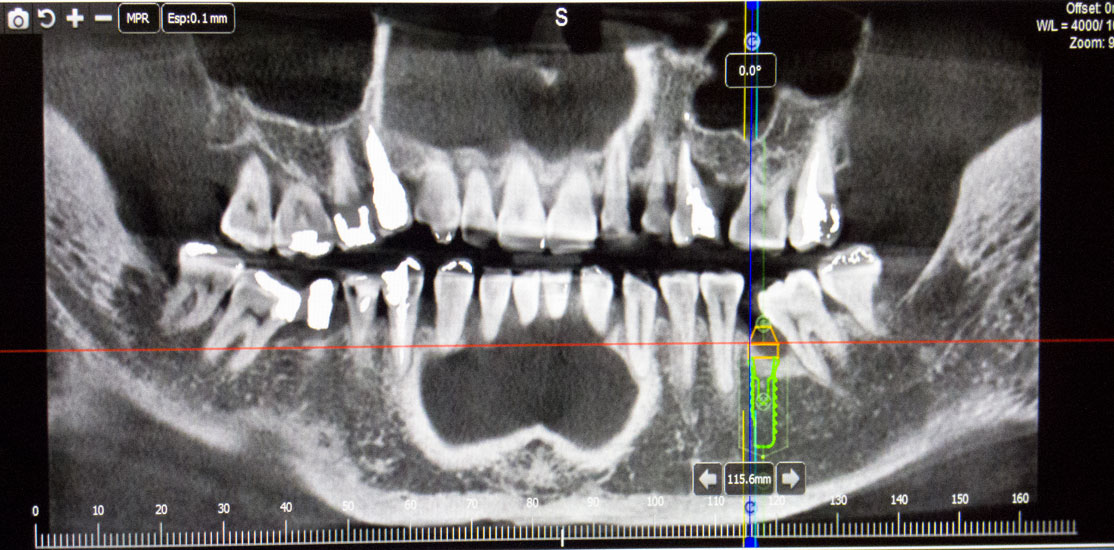

Con este Scaner obtenemos imágenes tridimensionales de la región bucofacial, dientes, hueso maxilar y mandibular, zona sinusal, etc.,  permitiéndonos evaluar con gran precisión el estado del paciente que acude a nuestra consulta, realizando un diagnóstico preciso, que nos posibilita estructurar el mejor tratamiento en cada circunstancia, evitando falsas expectativas y la frustración que conlleva el fracaso de tratamientos inadecuados por su errónea planificación.

La información  aportada por la tecnología 3D nos permite la realización de técnicas innovadoras de regeneración ósea guiada con coágulo del propio paciente, en zonas de gran pérdida de hueso, produciendo resultados altamente predecibles que nos facilitan restaurar la función masticatoria y estética, que los tratamientos convencionales no consiguen.

Las imágenes obtenidas mediante tecnología 3D, nos aportan información fiable de la zona bucodental que requiere tratamiento quirúrgico o conservador, minimizando en gran medida las complicaciones que pueden producirse si no disponemos de ella.